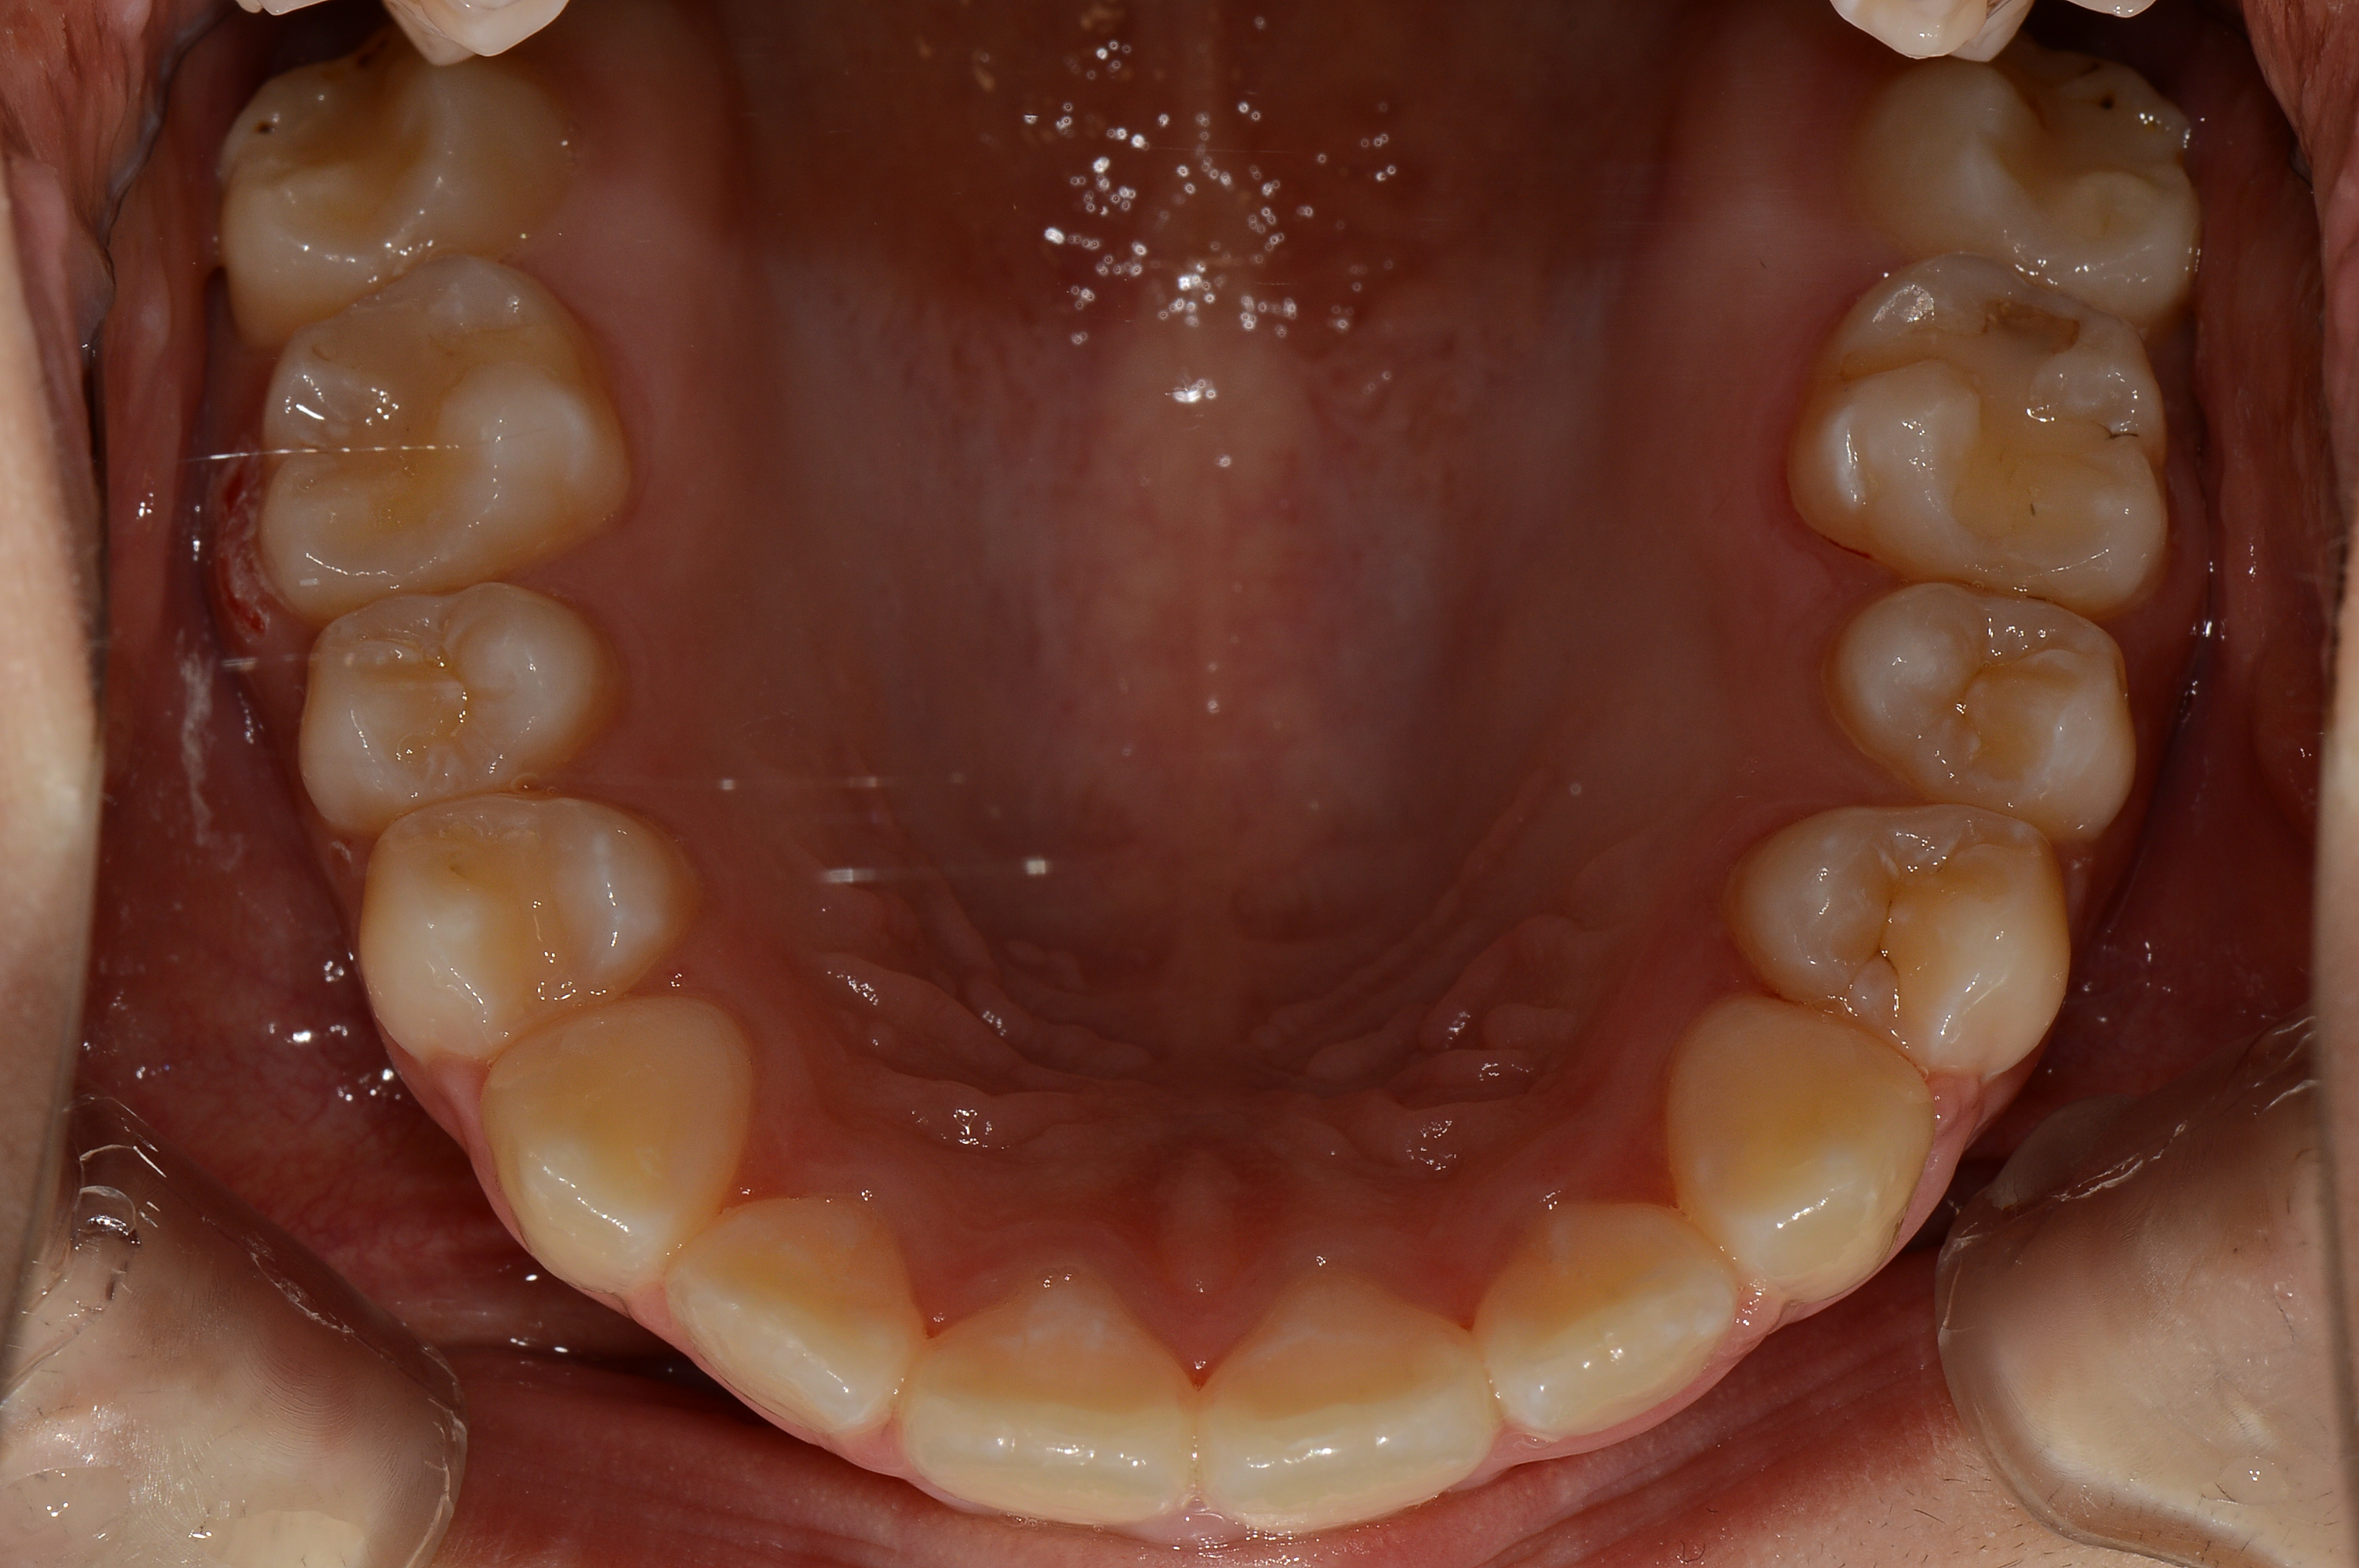

치료 전 사진입니다.